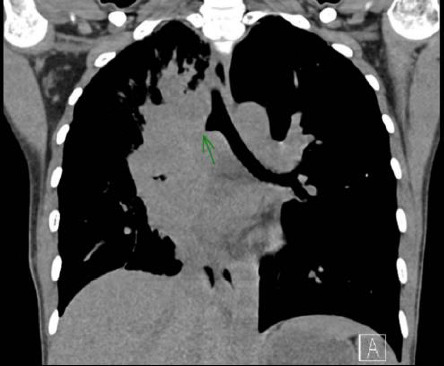

Background: Aspergillus tracheobronchitis (AT) is an uncommon yet severe form of invasive pulmonary aspergillosis, with a notably low incidence among individuals living with HIV infection-accounting for merely 4.5% (7 out of 156 cases) in recent reviews. The advent of modern antiretroviral therapy (ART) has significantly altered the landscape of opportunistic infections in HIV, rendering conditions like AT rare in well-controlled cases. Case Presentation: We present the case of a woman in her mid-20s with well-managed HIV infection who experienced a 4-week history of fever and dyspnea. Diagnostic procedures, including bronchoscopy, revealed granulation tissue obstructing her right main bronchus. Cultures confirmed infection with Aspergillus fumigatus, leading to a diagnosis of AT. Despite initial positive response to voriconazole treatment, the patient developed severe hemoptysis and unfortunately succumbed to the complication. Conclusion: This case underscores the critical need for healthcare providers to consider AT in the differential diagnosis of respiratory symptoms in HIV-positive patients, even when HIV is well-controlled with ART. Early recognition and prompt antifungal therapy are essential for improving outcomes. Clinicians should remain vigilant for severe complications like hemoptysis, which can occur despite appropriate therapy. This report highlights the ongoing necessity for vigilance and proactive intervention in the care of individuals living with HIV.